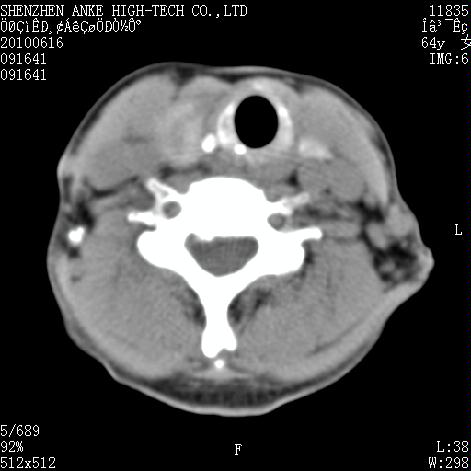

标题: CT27132:患者女,64岁,颈部及全身多处包块,现觉吞咽困难4 [打印本页]

标题: CT27132:患者女,64岁,颈部及全身多处包块,现觉吞咽困难4

右侧甲状腺占位,肿瘤可能性大,癌

右侧甲状腺癌伴右颌下腺淋巴结转移

右侧甲状腺癌伴淋巴结转移

右侧甲状腺癌伴淋巴结转移可能性大